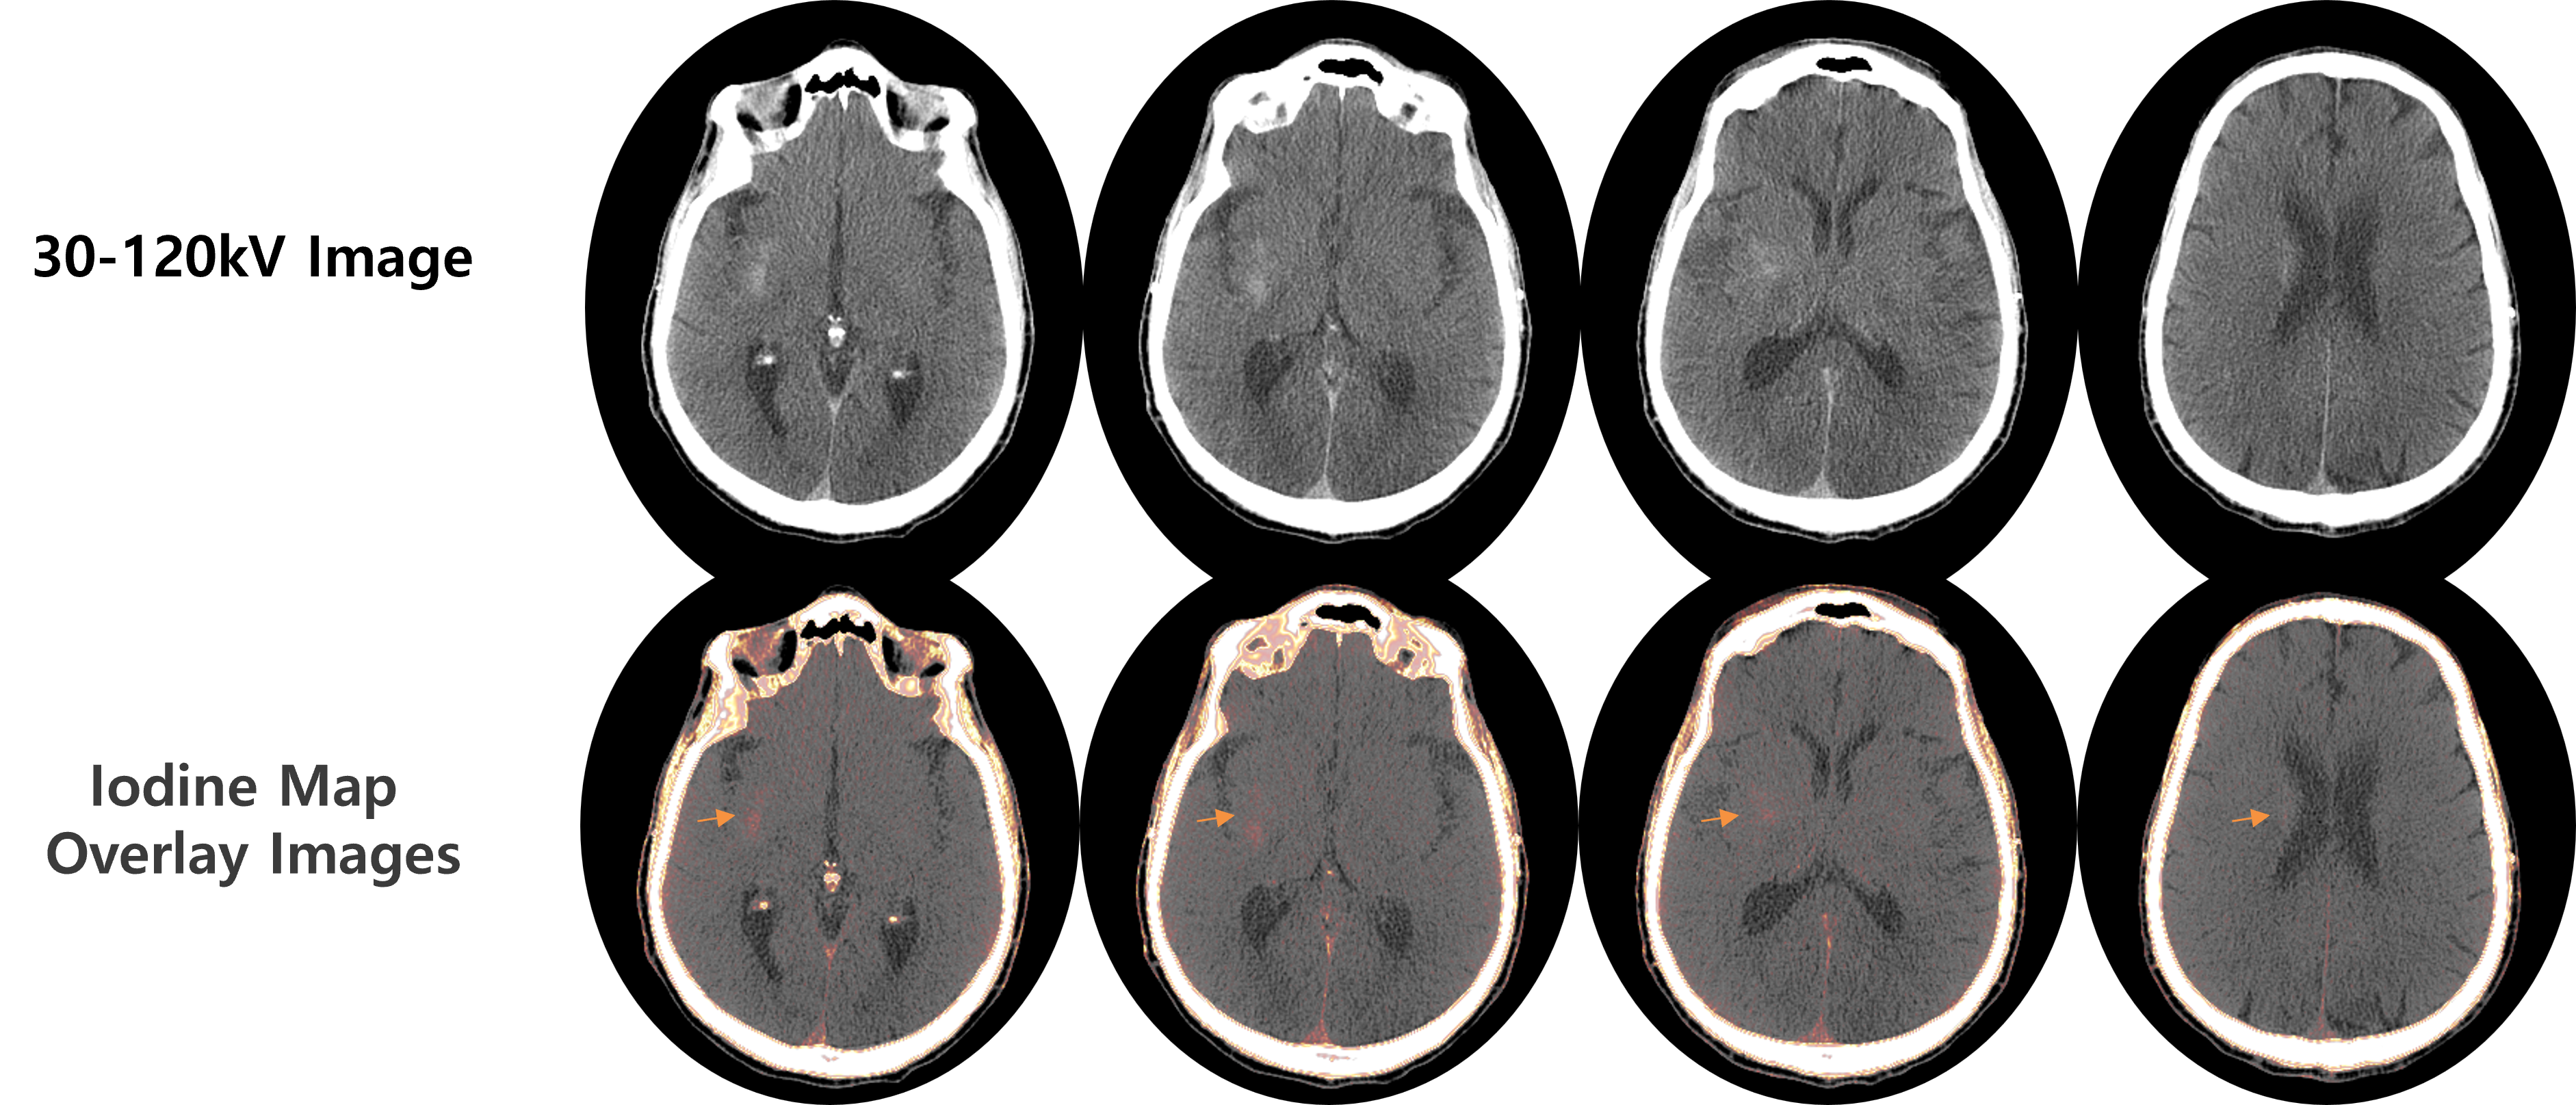

- Results of VMI with OmniTom Elite PCD

- Neuro ICU Patient (Intracerebral Hemorrhage)

- Differentiating hemorrhagic and non-hemorrhagic (iodine staining) lesions

- The blood brain barrier breakdown without hemorrhage by thrombectomy